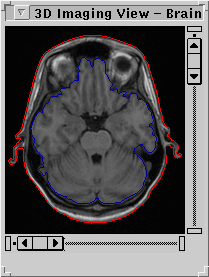

Figure 5. On the left

side; boundary based segmentation result. Scalp and cortex

are surrounded by chain links. On the right side;region

based segmentation result representing the brain, cerebrospinal

fluid and multiple sclerosis plaques.